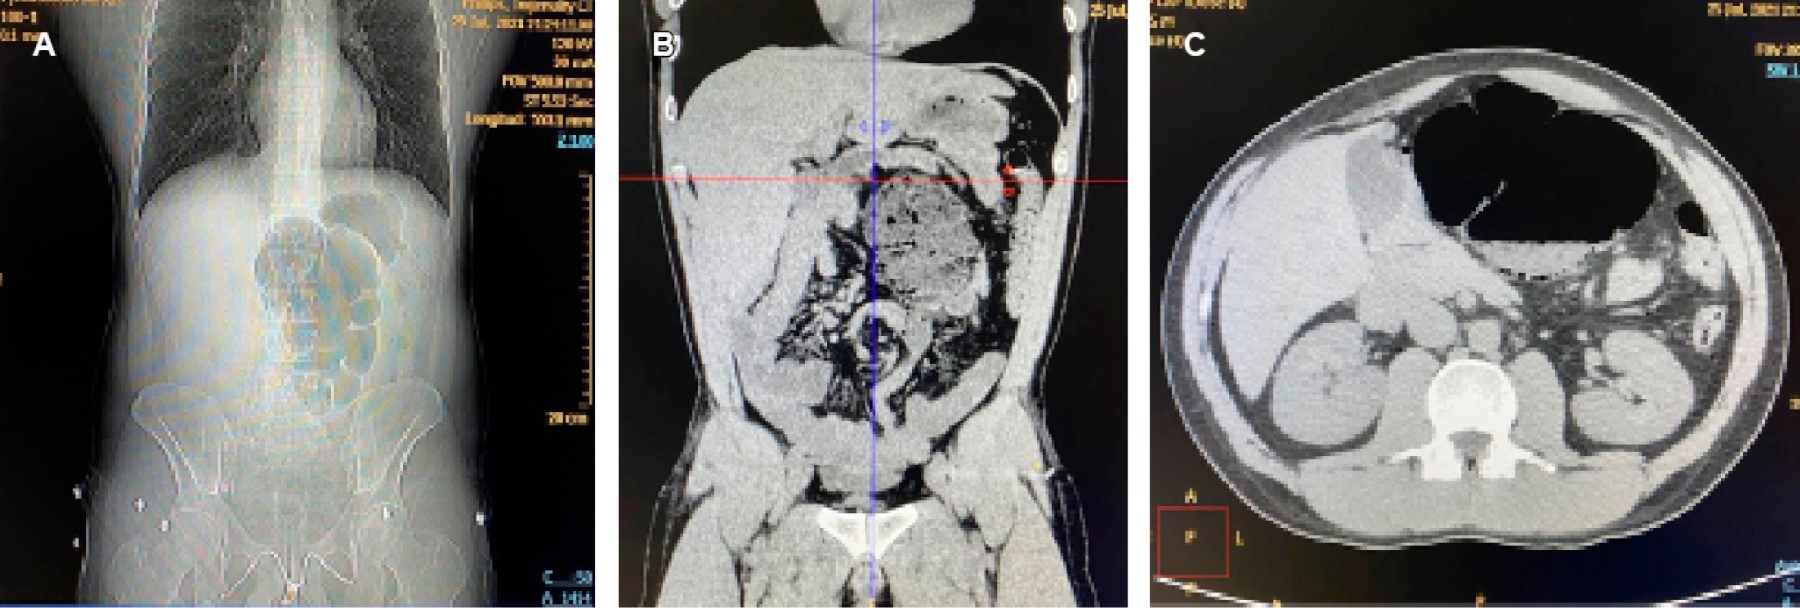

El laboratorio mostró leucocitos 12,000 × 103/μL con neutrofilia sin bandas. En la tomografía computarizada (TC) simple de abdomen (Figura 1) se observó imagen sugestiva de vólvulo del ciego con neumatosis de su pared y datos de malrotación intestinal. Se realizó laparotomía exploradora, encontrando colon con el ciego volvulado con gran dilatación sin datos de isquemia severa, el ciego en la línea media a nivel del ángulo de Treitz, el intestino delgado totalmente del lado derecho del abdomen; el colon derecho se encontró fijo por brida hacia la región del ángulo de Treitz. Se devolvuló el ciego recuperando su vascularidad, reparando dos desgarros seromusculares producidos por la dilatación; se descomprimió el colon de manera anterógrada; se realizó procedimiento de Ladd con sección de las bandas de adherencias hacia ángulo de Treitz y pared abdominal (Figura 2), ya liberado el colon se colocó del lado izquierdo del abdomen y el intestino delgado del lado derecho. Se realizó TC de control postoperatoria (Figura 3). La evolución fue satisfactoria y sin complicaciones.

La malrotación intestinal está determinada por una alteración total o parcial del intestino medio, rotando 270° en sentido antihorario alrededor el eje de la arteria mesentérica superior durante el desarrollo embrionario.1,2 La presentación típica en el adulto es el vólvulo del intestino medio con obstrucción del intestino delgado. La TC es de elección3 tanto en malrotación con oclusión como de apendicitis.4 Los hallazgos típicos son una relación inversa de la arteria mesentérica superior y vena mesentérica superior, apariencia arremolinada de la vasculatura entrando en el vólvulo (signo del remolino), asas del intestino delgado en la parte superior derecha, falta de visualización del ciego en fosa iliaca derecha, dilatación de asas duodenales y ángulo duodenoyeyunal a la derecha (signo de sacacorchos) (Figura 1).

Figura 1